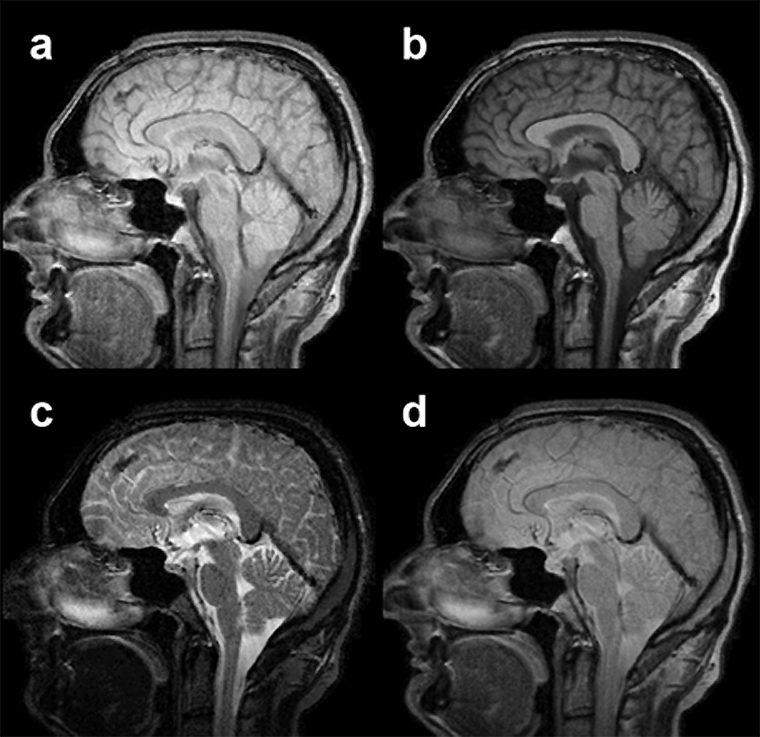

Figura 15-06:

Examples of multichannel images: (a) proton-density-weighted, (b) T1-weighted, and (c) T2-weighted ima­ges of a slice through the brain. The anatomic location of the pi­xels is ex­act­ly the same; according to ima­ge weight­ing the pixel representation is dif­fe­rent.

(d) is a pixel-by-pixel compilation of images a-c. This synthetic image does not reveal any additional dia­gnos­tic in­for­ma­tion.